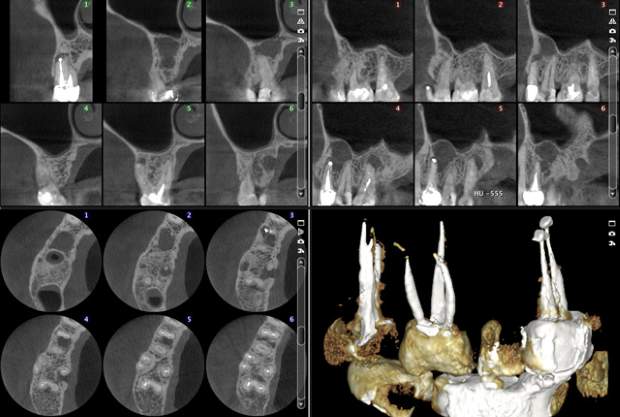

Bez redukcji szumów

Po użyciu filtra szumów Planmeca AINO

Bez usuwania artefaktów

Z użyciem algorytmu usuwania artefaktów Planmeca ARA

Planmeca ProMax 3D s Ø50x50 mm, rozmiar woksela 75µm

Planmeca ProMax 3D Mid Ø40x50 mm, rozmiar woksela 75µm